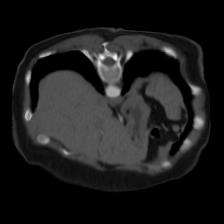

In clinical practice, well-aligned multi-modal images, such as Magnetic Resonance (MR) and Computed Tomography (CT), together can provide complementary information for image-guided therapies. Multi-modal image registration is essential for the accurate alignment of these multi-modal images. However, it remains a very challenging task due to complicated and unknown spatial correspondence between different modalities. In this paper, we propose a novel translation-based unsupervised deformable image registration approach to convert the multi-modal registration problem to a mono-modal one. Specifically, our approach incorporates a discriminator-free translation network to facilitate the training of the registration network and a patchwise contrastive loss to encourage the translation network to preserve object shapes. Furthermore, we propose to replace an adversarial loss, that is widely used in previous multi-modal image registration methods, with a pixel loss in order to integrate the output of translation into the target modality. This leads to an unsupervised method requiring no ground-truth deformation or pairs of aligned images for training. We evaluate four variants of our approach on the public Learn2Reg 2021 datasets \cite{hering2021learn2reg}. The experimental results demonstrate that the proposed architecture achieves state-of-the-art performance. Our code is available at https://github.com/heyblackC/DFMIR.